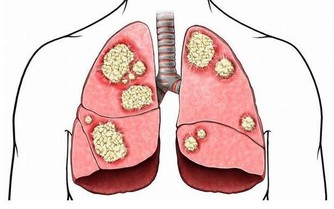

肺部,掌管我們身體中氧氣的輸入和輸出。肺部的健康對我們生命活動都起到著很重要的作用。但是,很多人每天能卻都在做著傷害肺部健康的事情。那就是抽煙。

據研究顯示,抽煙是當今社會導致肺癌的罪魁禍首之一。約40%的慢性阻塞性肺病由吸煙直接引起。吸煙指數(每天吸菸支數×菸齡)大於400者,患肺癌的機率將升高7倍之多。而對於長期吸二手煙的人來說,患肺癌的機率將會提高25%以上。

很多人,或許有個疑問,那就是,戒菸後肺部真的還能恢復健康嗎?

專家表示,戒菸後肺部是可以慢慢恢復的。若在35歲前成功戒菸,你的預期壽命會同常人一樣。

戒菸24小時後: 血液系統、血壓及心臟健康等會逐漸恢復正常。

戒菸48小時後: 消除大部分尼古丁,嗅覺與味覺也逐漸變更好。

戒菸3~9個月後:呼吸問題變好了,肺部開始逐漸恢復健康。

戒菸1年以後:冠狀動脈疾病風險降低50%

戒菸5年後:中風的風險降低至和不抽煙的人同樣水平。

戒菸10年後:患肺癌的機率達到了正常吸煙人的一半。

戒菸15年後:患冠心病的風險同不抽煙的人一樣。死亡的風險也恢復到了和不抽煙人一樣。